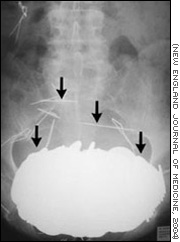

Una radiografía muestra el estómago del paciente lleno de monedas, collares y agujas.

A pesar de ello, los médicos se asustaron cuando le tomaron una radiografía. En la imagen, vieron una masa opaca enorme en su estómago que resultó pesar 5,4 kilos, tanto como algunas bolas que se emplean para jugar a las bochas. Era tan pesada que había empujado su estómago hacia abajo hasta ubicarlo entre sus caderas.